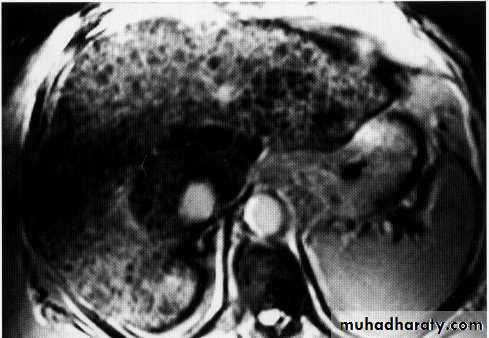

Hepatic mets.

Splenic U/ S

FNH

HCC